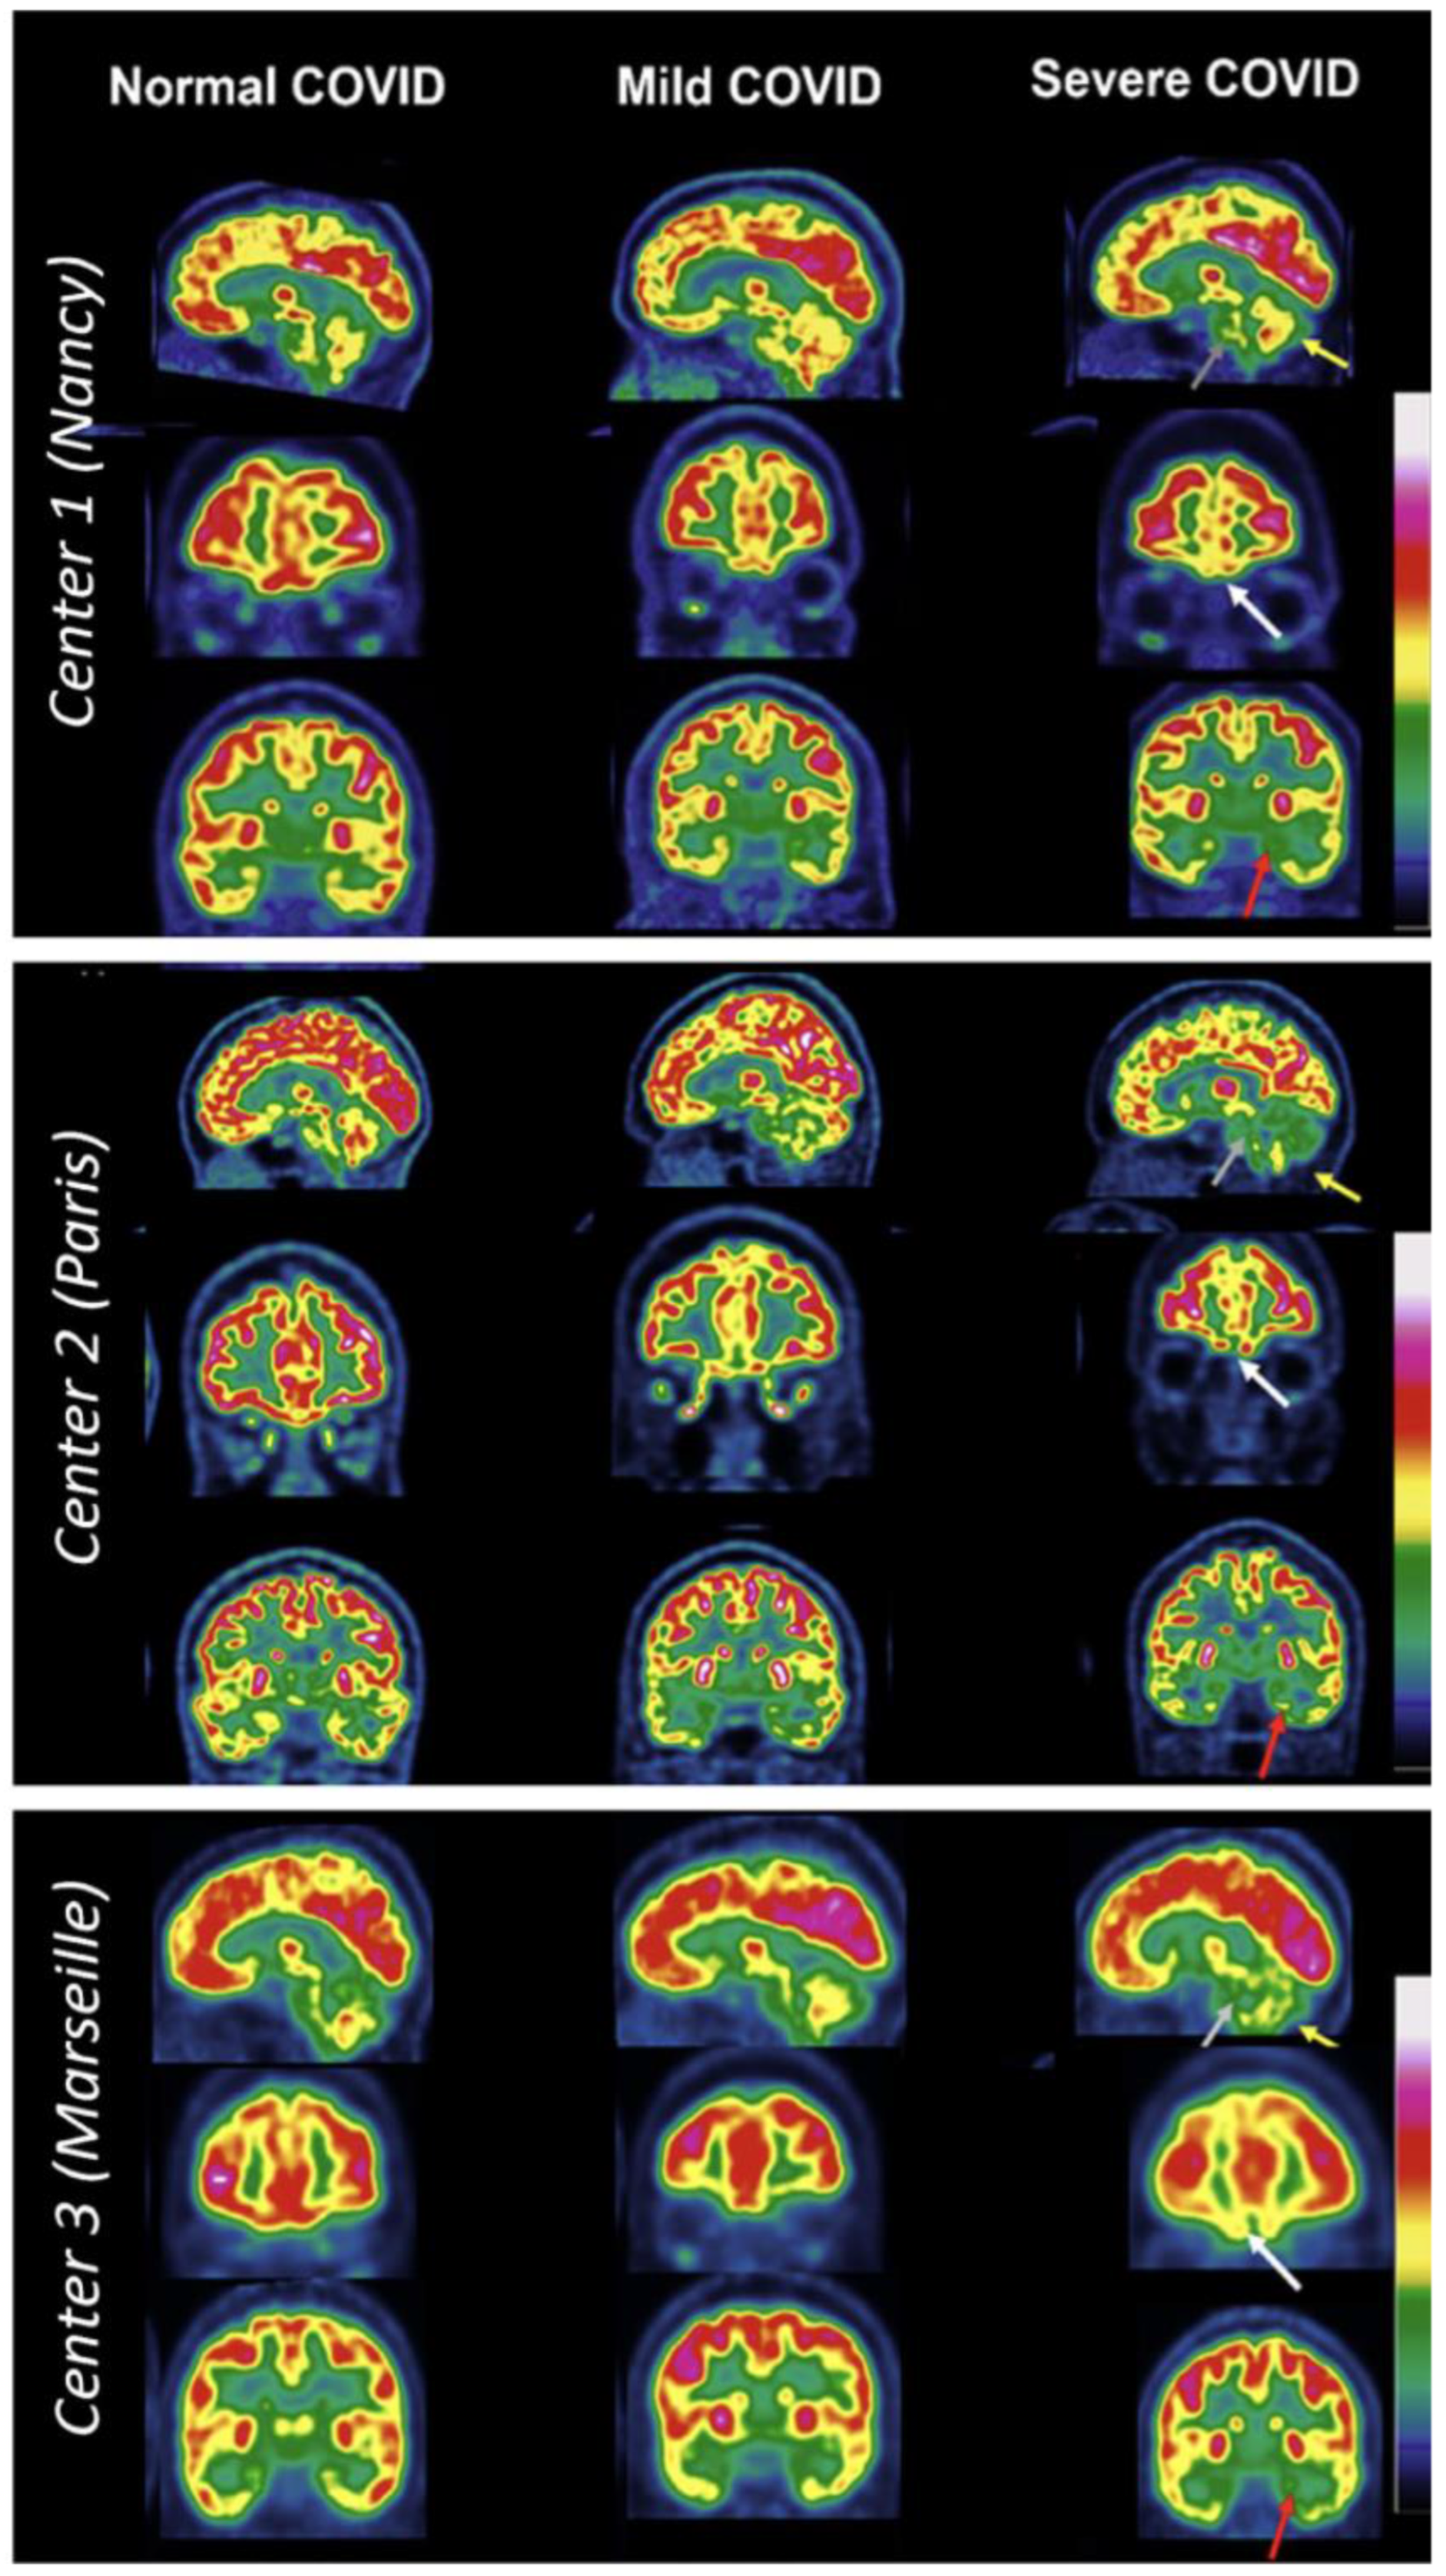

| Kas et al. [54] | Prefrontal, insular and subcortical | Cognitive and emotional disorders of varying severity remained with attention/executive disabilities and anxio-depressive symptoms | Approximately 6 months | Observational- prospective/7 subjects (4 males and 3 females; 2 had history of hospitalization) |

- Kas, A.; Soret, M.; Pyatigoskaya, N.; Habert, M.-O.; Hesters, A.; Le Guennec, L.; Paccoud, O.; Bombois, S.; Delorme, C. The Cerebral Network of COVID-19-Related Encephalopathy: A Longitudinal Voxel-Based 18F-FDG-PET Study. Eur. J. Nucl. Med. Mol. Imaging 2021, 48, 2543–2557. [Google Scholar] [CrossRef] [PubMed]